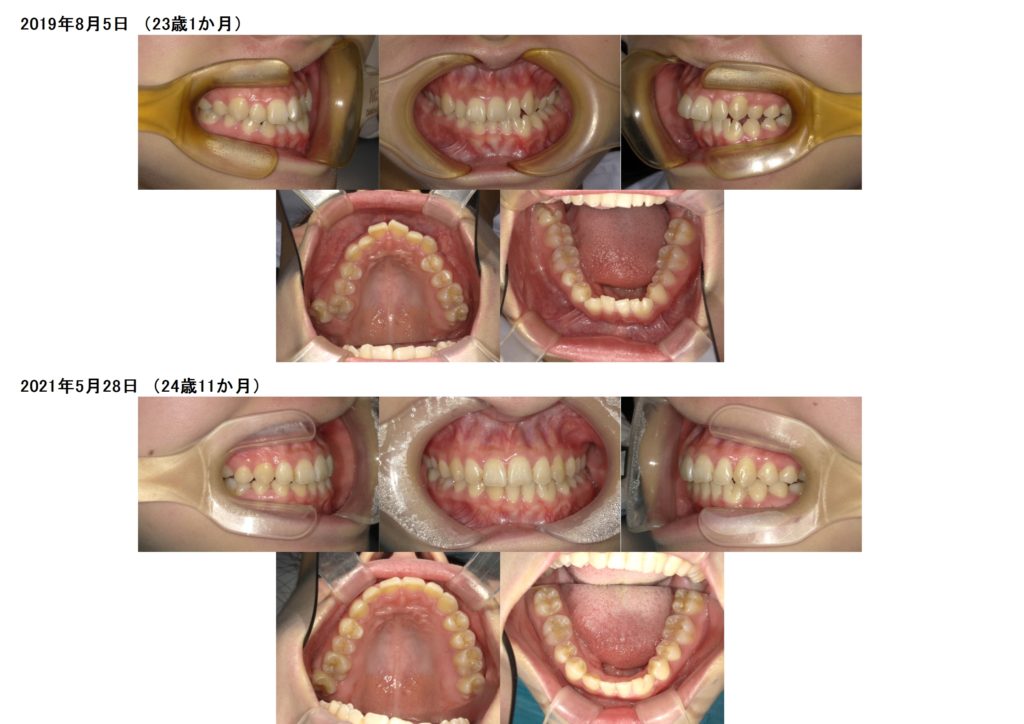

↑上が初診時のお口の中になります。

左下の部分が癒合歯になります。

少しだけ歯が大きいのです。

マウスピースを使用して治療が完了しました。

今はしっかりと歯並び、噛み合わせを定着させるために保定期間中になります。

このように、矯正治療をすると、目立ちにくくなりますし、噛み合わせも確立することができます。